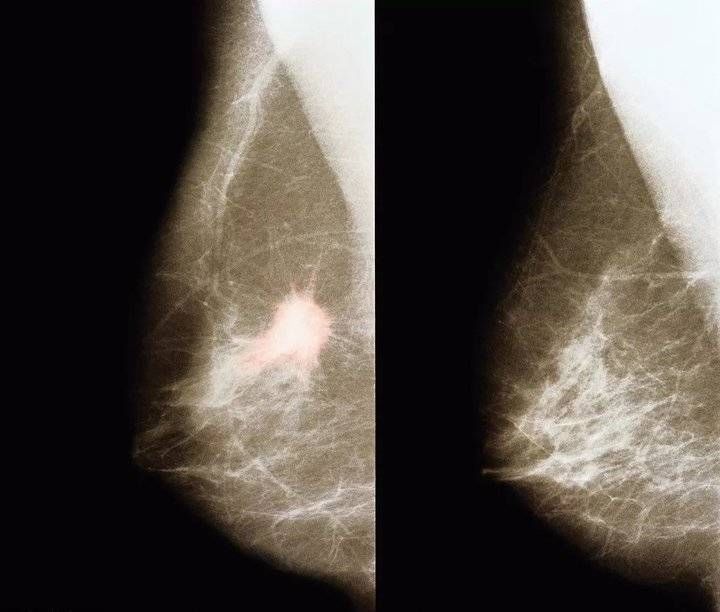

根据《中国乳腺疾病调查报告》显示:我国城市乳腺癌的死亡率增长了38.1%,乳腺癌已经成为威胁女性健康的“头号杀手”。

在面对乳腺的问题上,很多女性在初期出现一些轻微症状时,并不是太在意,总觉得没什么大碍,于是一拖再拖,从而酿成严重的后果。

乳房检查是乳腺疾病非常重要的检测手段,下面教大家一些自查的方法: